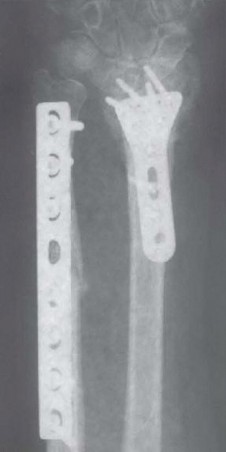

Hardware selection is the next critical step in our pre-operative workflow. Modern ulnar shortening is overwhelmingly performed using dedicated, precision osteotomy systems. These sets feature sophisticated sliding jigs that allow for highly controlled, parallel osteotomy cuts and built-in compression mechanisms. We generally prefer a 6-hole or 7-hole dynamic compression plate designed specifically for the ulnar diaphysis. The debate between a transverse versus an oblique osteotomy heavily favors the oblique cut (typically angled at 45 degrees). The oblique osteotomy vastly increases the surface area for bone healing, allows for the placement of an interfragmentary lag screw through the plate, and provides superior rotational control during compression.

Following the resection, the compression device integrated into the jig is activated. We slowly and deliberately compress the osteotomy site until